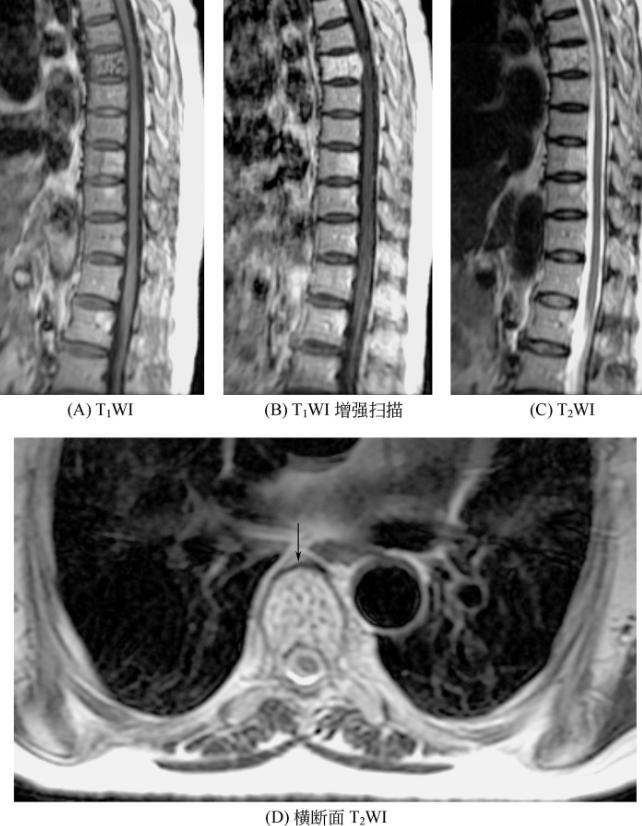

骨血管瘤在MRI上表现为T1WI和T2WI上均为高信号,椎体的血管瘤,其内可见粗大而松散的低信号骨小梁,在横断面上表现为低信号的斑点,在矢状面或冠状面上表现为低信号的栅栏状影(图3)。长骨的血管瘤,血管丰富者可显示为骨髓腔内点状和短条状低信号。

图3 血管瘤矢状位胸4、胸7、胸8、胸9、胸11椎体可见短T1长T2信号,胸4、胸7椎体内病变呈栅栏状改变。横断面可见胸4椎体普遍信号增高,内见多发点状低信号影。增强扫描:椎体内病变可见明显强化。